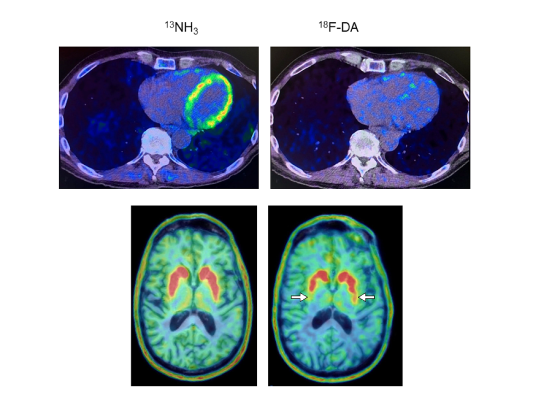

Heart and brain PET scans from a study participant who developed Parkinson’s disease support a “body first” progression. The top pair of PET scans image show low 18F-dopamine-derived radioactivity in the heart (right, with 13N-ammonia PET scan on left). Later, brain scans showed a loss of dopamine-producing neurons and the individual developed symptoms of the disease. Goldstein lab, NINDS

In the present study, the research team led by Dr. Goldstein found that at-risk individuals with low 18F-dopamine-derived radioactivity in the heart were highly likely to develop Parkinson’s or Lewy body dementia during long-term follow-up, compared to individuals with the same risk factors but with normal radioactivity. PET scans work by using a radioactive tracer to visualize metabolic or biochemical processes in body organs.

Of the nine individuals with low cardiac 18F-dopamine-derived radioactivity at their first scan, eight were diagnosed later with Parkinson’s or Lewy body dementia. Only 1 of 11 participants with normal initial radioactivity developed a central Lewy body disease. All nine participants who developed a Lewy body disease had low radioactivity before or at the time of diagnosis.

“We think that in many cases of Parkinson’s and dementia with Lewy bodies the disease processes don’t actually begin in the brain. Through autonomic abnormalities the processes eventually make their way to the brain,” Dr. Goldstein said. “The loss of norepinephrine in the heart predicts and precedes the loss of dopamine in the brain in Lewy body diseases.”